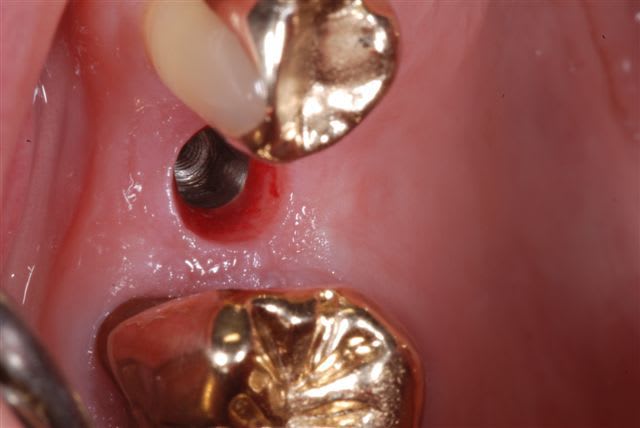

comparaison photos prises avec flash Metz 15 et sigma 140 DG, même boitier (Nikon D80) iso 100, f32, i-ttl, mise au point manuelle.

bon alors pour faire comme suggéré par D57:

(f16, iso 100, même cadrage, boitier et rapport d'agrandissement, i-ttl)

voilà typiquement la différence obtenue entre ces deux flashs